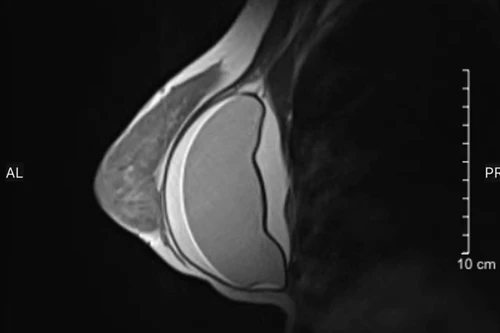

Nữ bệnh nhân 31 tuổi bị vỡ túi ngực sau 4 năm đi nâng ngực

Đặt túi silicon nâng ngực loại “xịn” nhưng vẫn phải nhập viện cầu cứu bác sĩ